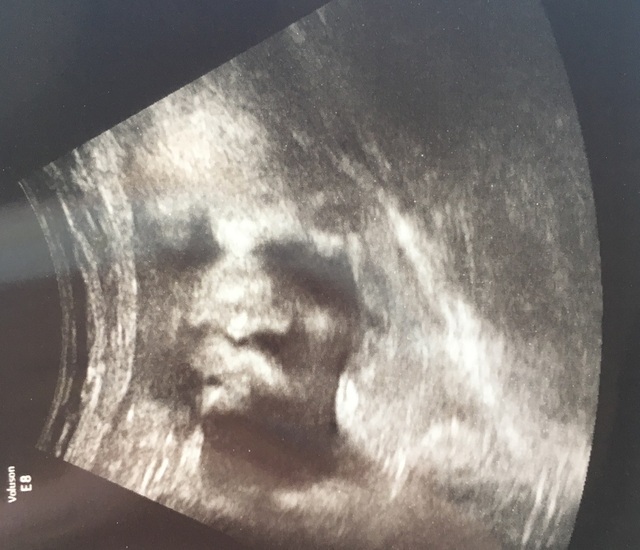

28週3日(28w3d・女の子)|しのまむ さん(25歳)

エコー写真撮影時のエピソード:

毎回検診では背中の方を向いていたり 手で隠したりして、なかなか顔を見せてくれなかったのですが、生まれる1週間前の健診でやっと顔を見せてくれた時のエコーです。

わたしは1発でここが目だな!など 顔と認識できて うれしくてすぐ旦那に送ったけど、旦那はどこが目?鼻?と 全然顔と認識できなかったようで 感動を分かり合えかったのが悲しかったです。

でもここが目でね口がこれで、、 と説明したら やっとわかったみたいで ペチャ鼻はオレ譲りだなと、うれしいそうにしていてとても微笑ましかったです。

早く会いたいなー!と言っていたら 予定日よりも1週間早く出て来てくれました。